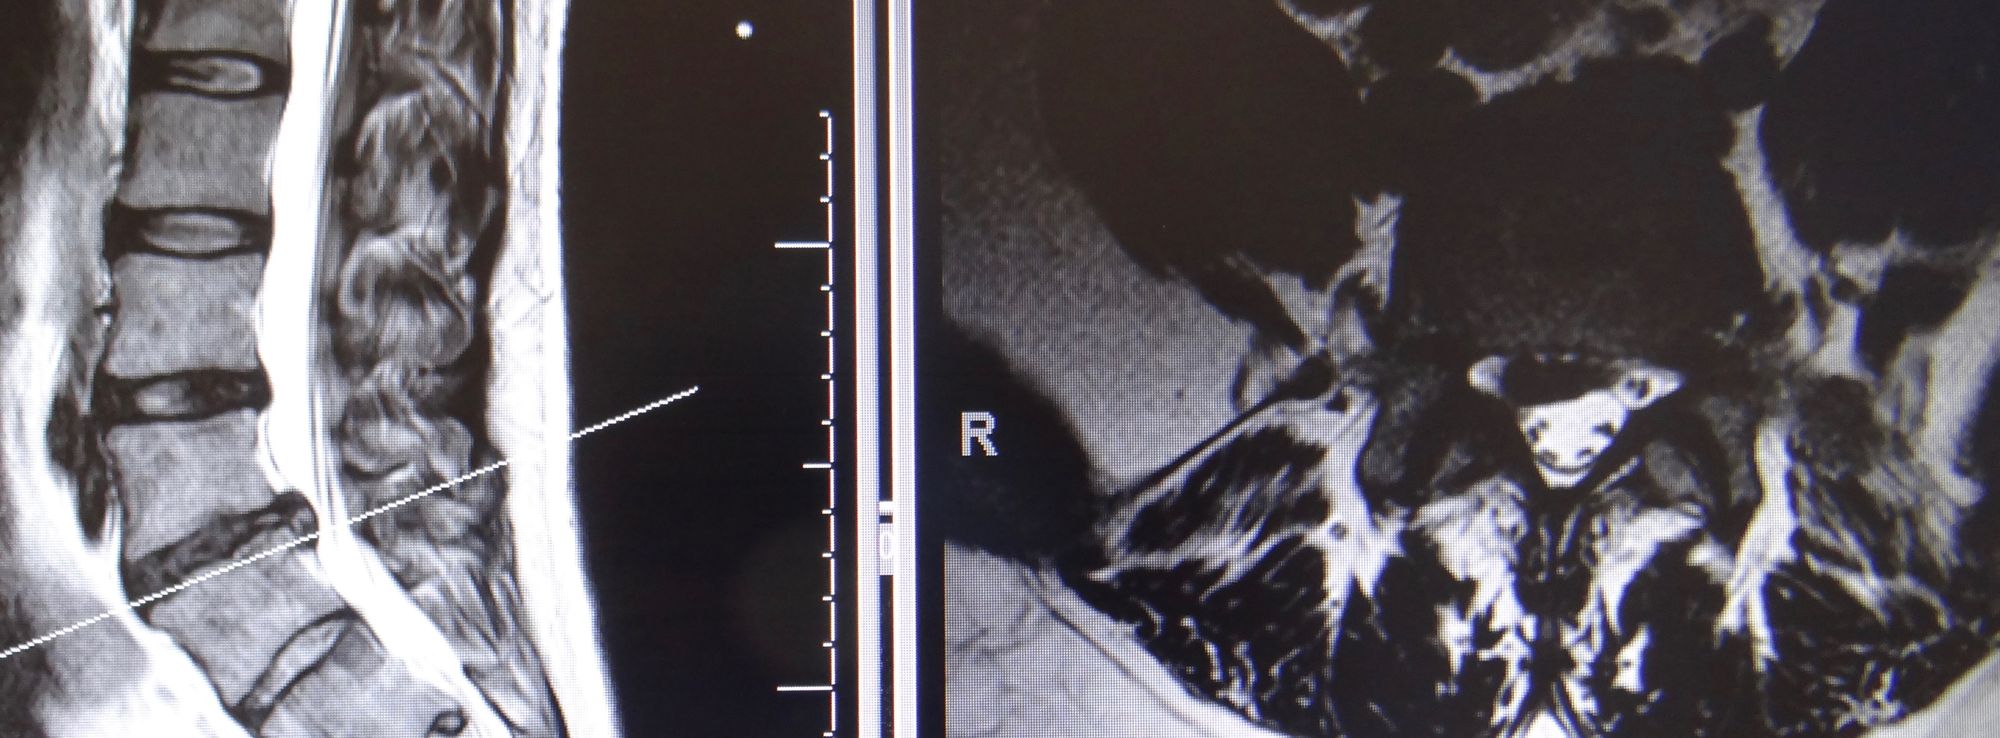

Neurochirurgie du rachis

C’est l’ensemble de la prise en charge médicale ou chirurgicale des pathologies touchant la colonne vertébrale, la moelle épinière et les nerfs périphériques. Le traitement touche aussi bien la colonne cervicale, dorsale, lombaire et du sacrum. Les pathologies qui touchent la colonne vertébrale sont les affections congénitales, traumatiques, tumorales, infectieuses et dégénératives (liées à l’âge).

L’hernie discale est en lien avec l’usure du disque intervertébral, se trouvant entre deux vertèbres. Suite à un traumatisme ou un phénomène dégénératif par usure, du matériel discal provenant du cœur du disque fait sailli dans le canal rachidien et vient comprimer une racine nerveuse provoquant, entre autres, la fameuse sciatique (radiculopathie).

En effet, les symptômes provenant d’une hernie discale, sont une douleur au niveau du dos (lombalgie) avec irradiation de la douleur dans la jambe jusqu’au pied (sciatalgie). Des signes sensitifs, tels que des fourmillements, diminution de la sensibilité dans les jambes ou les pieds sont souvent associés. Il apparaît également, parfois, une perte de force dans les membres inférieurs, provoquant des difficultés à la marche. Dans de rares cas, il peut arriver des troubles sphinctériens, se traduisant par une incontinence urinaire ou fécale (perte d’urine ou de selles involontaire).

Le traitement d’une hernie discale consiste, dans la majorité des cas, au repos associé aux médicaments antidouleurs ( anti-inflammatoires, dérivés de la morphine, etc.), ce qui permet d’aboutir à une guérison spontanée. La douleur dans la jambe tend à disparaître relativement rapidement, alors que la faiblesse ou les troubles sensitifs peuvent perdurer.

Dans les cas de déficit moteur et/ou sensitif, ou de persistance/majoration de la douleur, une chirurgie de décompression du nerf est proposée. L’intervention consiste en une microdiscectomie (curetage du disque) avec résection de l’hernie.